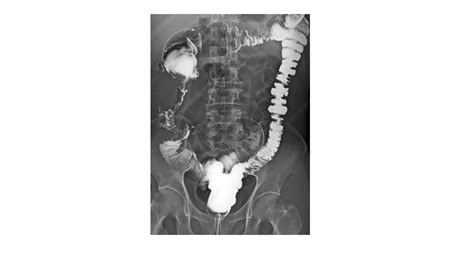

The Small Bowel Follow Through (SBFT) is a radiological examination that uses X-rays to visualize the small intestine. This procedure is particularly useful for detecting abnormalities such as strictures, obstructions, tumors, and inflammatory conditions like Crohn’s disease. The SBFT involves ingesting a barium solution, which coats the lining of the small intestine, making it visible on X-ray images.

• X-ray Imaging: As the barium solution moves through the small intestine, a series of X-ray images are taken at regular intervals. This allows the radiologist to observe the movement of the barium and identify any abnormalities.

• Duration: The entire procedure can take several hours, as the barium solution needs time to pass through the small intestine. Patients may be asked to change positions frequently to ensure that all parts of the intestine are visualized.

Interpreting the results of an SBFT requires expertise in radiology. The radiologist will examine the X-ray images for any signs of abnormalities. Common findings include:

The Small Bowel Follow Through is a valuable tool for diagnosing a variety of conditions affecting the small intestine. Some of the most common conditions include: